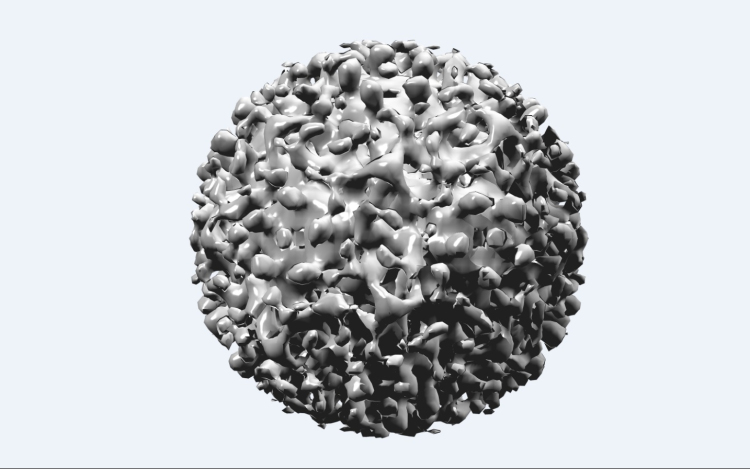

Forrás: mti - illusztráció: pixabay

A Vírusos Májbetegek Országos Egyesülete (Vimor) szeptember 15-én, szombaton országos szűrést szervez a hepatitis C vírussal fertőzöttek felderítésére.

A szervezet közölte, a szűrés célja a fertőzöttek felkutatása azért, hogy minél hamarabb megkezdhessék náluk a kezelést. A betegség ma már gyógyszeres kezeléssel jól gyógyítható.

Szakmai becslések szerint Magyarország lakosságának körülbelül egy százalékát érintik a krónikus vírushepatitisz-fertőzések. Mivel e fertőzések húsz-ötven évig lappanganak, nem okoznak jellegzetes panaszokat, az érintettek nagy része nem is tud betegségéről és a fertőzőképességéről.

A hepatitis C szinte tünetmentesen, észrevétlenül rombolja a májat. Mire a jellegzetes tünetek jelentkeznek, addigra sokszor előrehaladott májkárosodás, májzsugor, májrák alakulhat ki. A fertőzés vérrel terjed, védőoltás nincs ellene - hívja fel a figyelmet a szervezet.

Veszélyeztetettek lehetnek többek között az egészségügyben dolgozók, a büntetés-végrehajtási intézetekben elhelyezettek, a hepatitis C fertőzöttekkel egy háztartásban élők, valamint szexuális partnereik, a hepatitis C-pozitív anyák gyermekei, továbbá az intravénás drogokkal élők.

A betegszervezet szerint mindenképpen érdemes szűrésre menniük azoknak is, akiknek tetoválásuk vagy testékszerük van, valamint akik 1993 előtt vért vagy vérkészítményt kaptak.